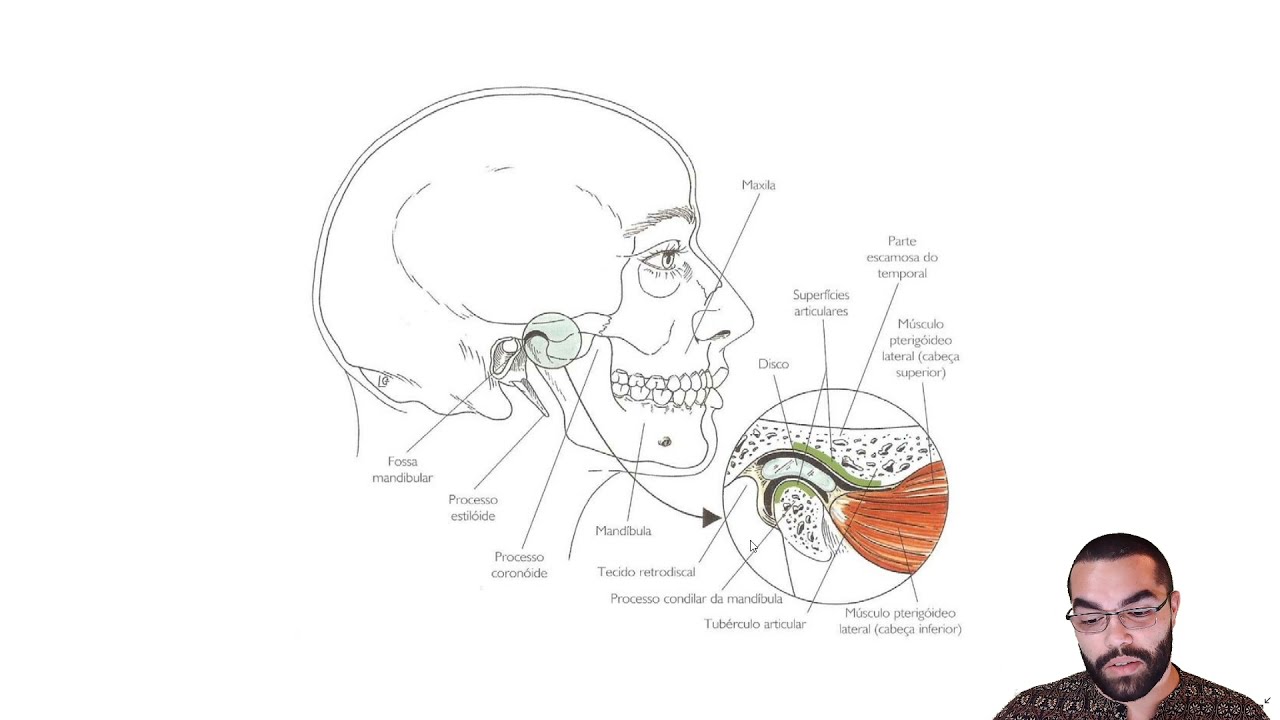

Tratamento cirúrgico das desordens articulares.

- Disfunção temporomandibular e dor orofacial

- Disfunção da ATM

• Studio 4 - Sala 1410 • Disfunções das ATM - articulação temporomandibular •

Quais são as principais especialidades de Raphael Márcio Egídio Cota?Raphael Márcio Egídio Cota é cirurgião buco-maxilo-facial, dentista. Te mostramos alguns dos serviços oferecidos pelo especialista graças à sua trajetória e vasta experiência: Enxertos ósseos dos maxilares, Excisao Parcial De Labio Por Lesao Com Rotacao De Retalho, Excisão Parcial De Lábio Com Enxerto Livre, Osteotomia Maxilar Superior, Osteoplastia Para Micrognatismo Com Ou Sem Implante De Silicone, Osteoplastia Da Mandibula Para Prognatismo, Reducao Cruenta Da Fratura Bilateral Da Mandibula, Extração do siso, Artroscopia da articulação temporomandibular, Consulta Cirurgia e Traumatologia Buco-maxilo-facial.